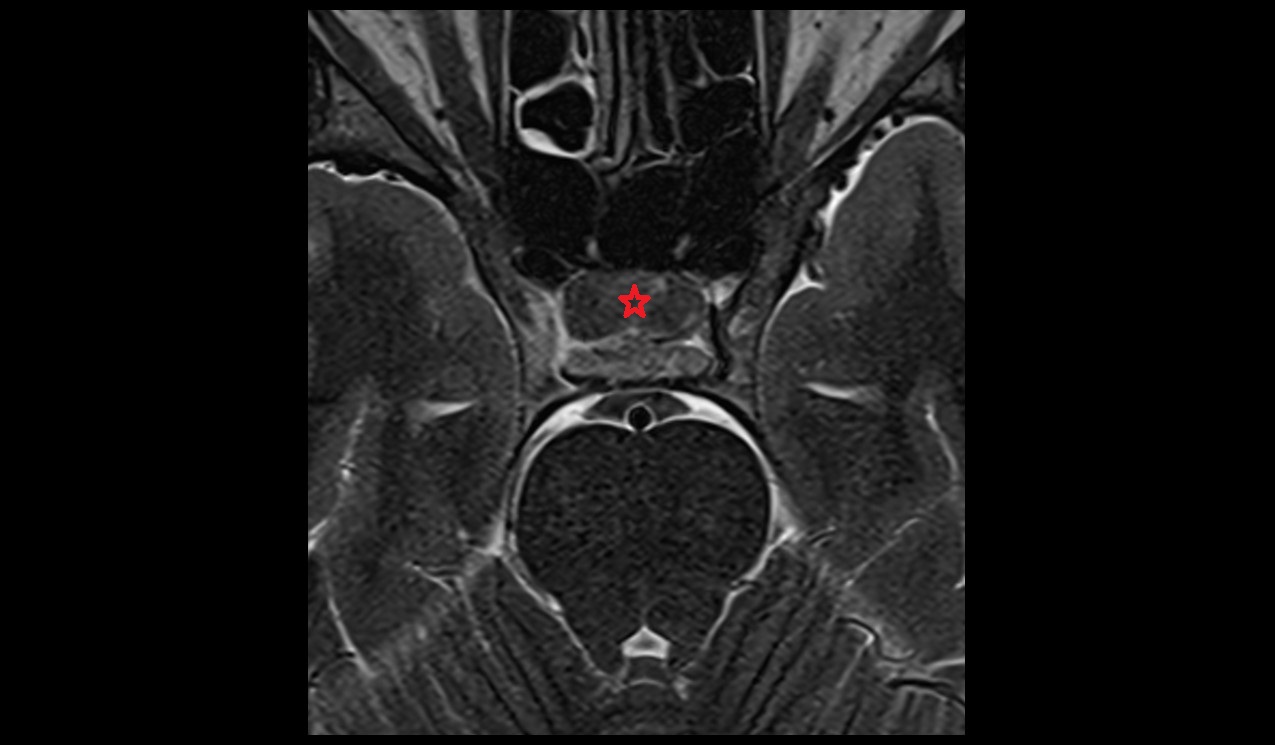

- Peripheral zone of prostate

- Anterior Fibromuscular Stroma of prostate

- Central zone of prostate

- Transitional zone of prostate